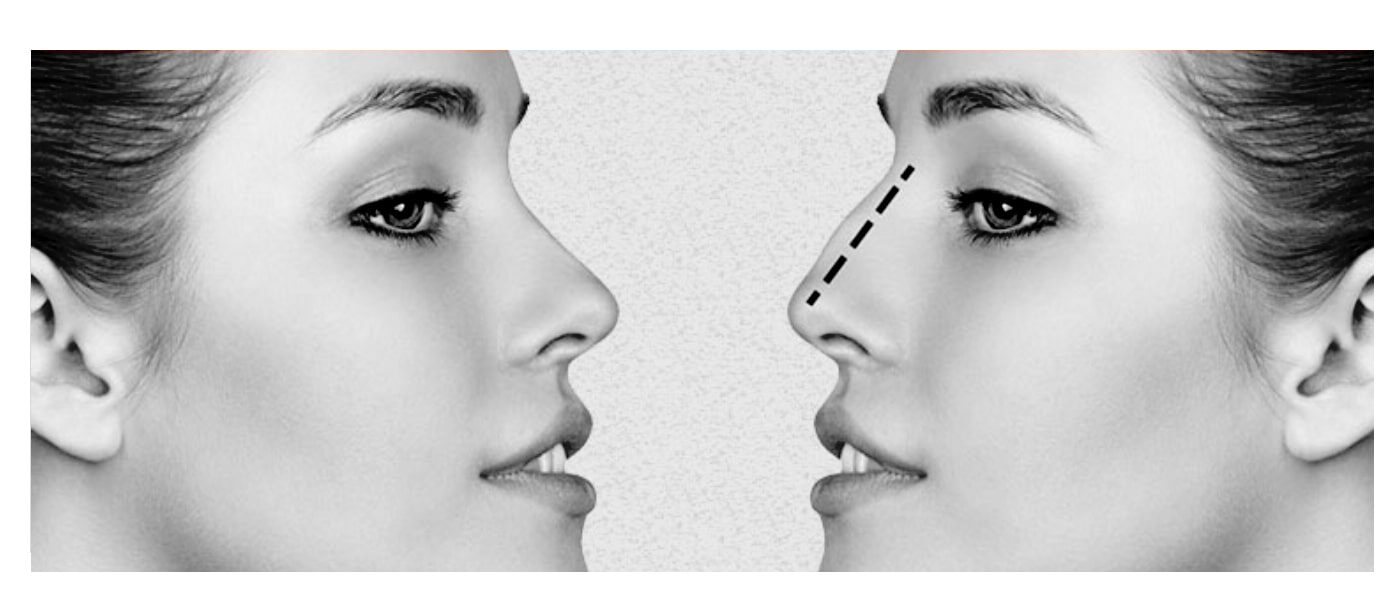

Nasal hump surgery without anesthesia:

This procedure is also known as rhinoplasty without surgery. There is no need for anesthesia to correct the hump above the nose. With just local anesthesia and splitting of the top of the nose, the bone is shaved to remove the hump and bulge on the nose.

The appearance of a bony nose is that they are curved or have a hump on the bridge of the nose. Bony noses are among the most ideal noses for cosmetic rhinoplasty because they have thin skin and less resistant tissue and cartilage.